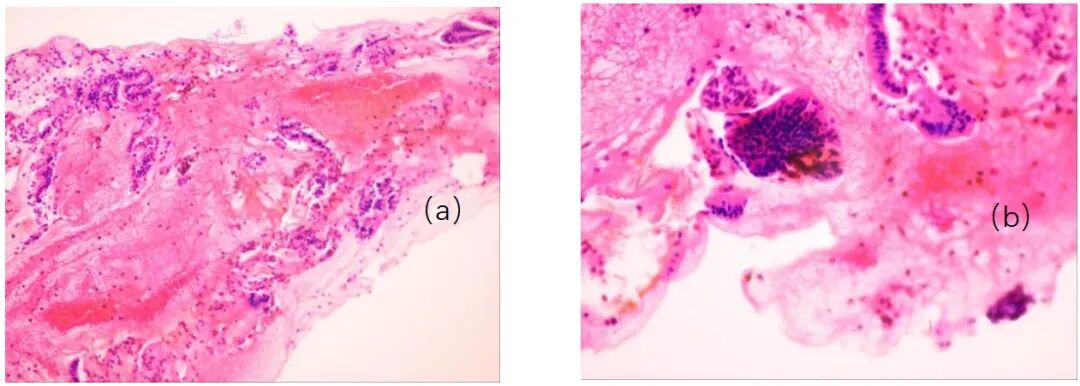

病史摘要:患者为 36 岁男性,主诉持续性腹痛 5 个月,伴黏液血便 1 个月,后进展为不完全性肠梗阻。3 年前确诊急性 B 淋巴细胞白血病,并行异基因造血干细胞移植,移植后发生累及口腔及皮肤的急性移植物抗宿主病,使用环孢素、芦可替尼治疗至腹痛发作。 诊疗过程:实验室检查示 D - 二聚体及超敏 C 反应蛋白升高,其余正常。结肠镜见乙状结肠及直肠黏膜充血等改变,CT